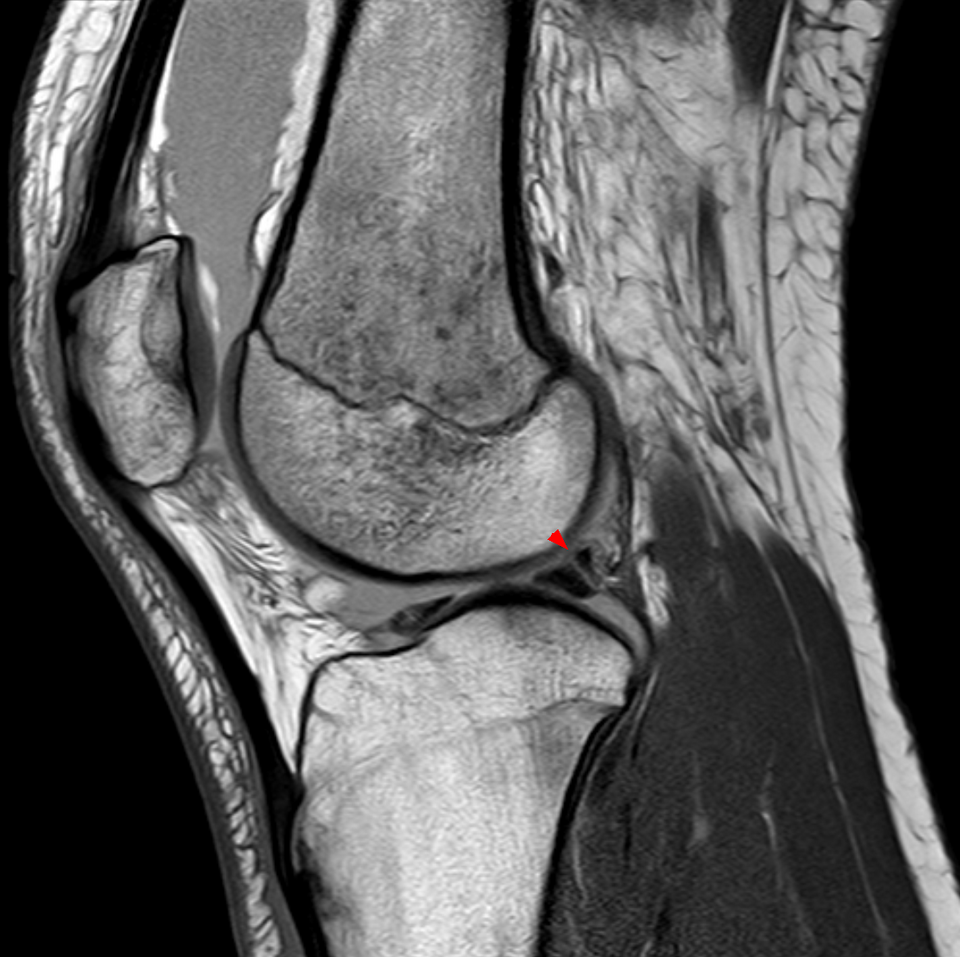

Knee with complete ACL rupture showing torn ligament, bone bruises on lateral femoral condyle and posterolateral...

Knee with medial meniscus tear (bucket-handle type) showing displaced meniscal fragment, joint effusion, and...

Degenerative knee with joint space narrowing, osteophytes, subchondral sclerosis, cartilage thinning, and Baker's cyst